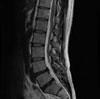

MRI検査

MRI(Magnetic ResonanceImaging)は、大きな磁石による強い磁場とFMラジオに使われているような電波を使って、体の断層画像を得る検査です。CTとの大きな違いは、X線を使わない画像診断です。

令和6年4月に新しく3T装置を導入し、より詳細な検査を行うことが出来るようになりました。また、開口径のより広いワイドボアを採用しています。身体の大きな方、狭いところが苦手な方にも対応することが可能です。